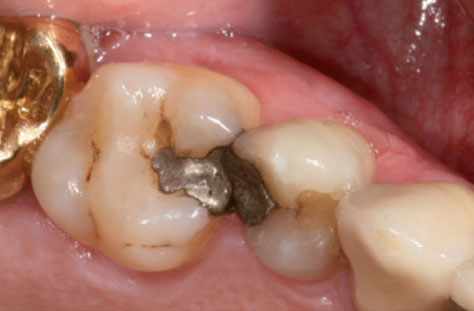

Amalgamentfernung

Metallbestandteile können in der Regel wenige Tage nach dem Einbringen in den Mund überall im Körper nachgewiesen werden.

Metallentfernung

Für verschiedene Metalle (Quecksilber, Gold, Platin, Kupfer, Kobalt, Aluminium) sind immunologische und krebserregende Wirkungen gut belegt.